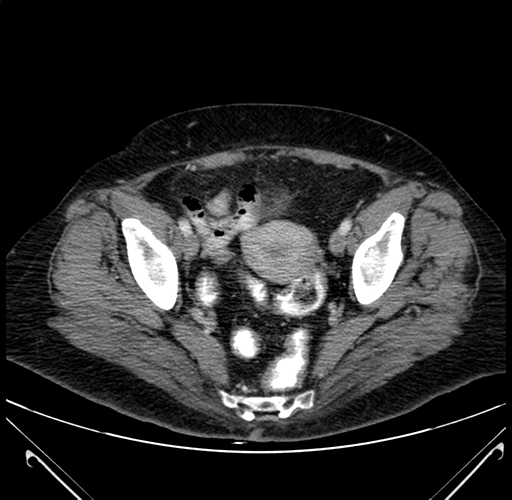

Pre-Chemo: Axial Venous

Axial Venous